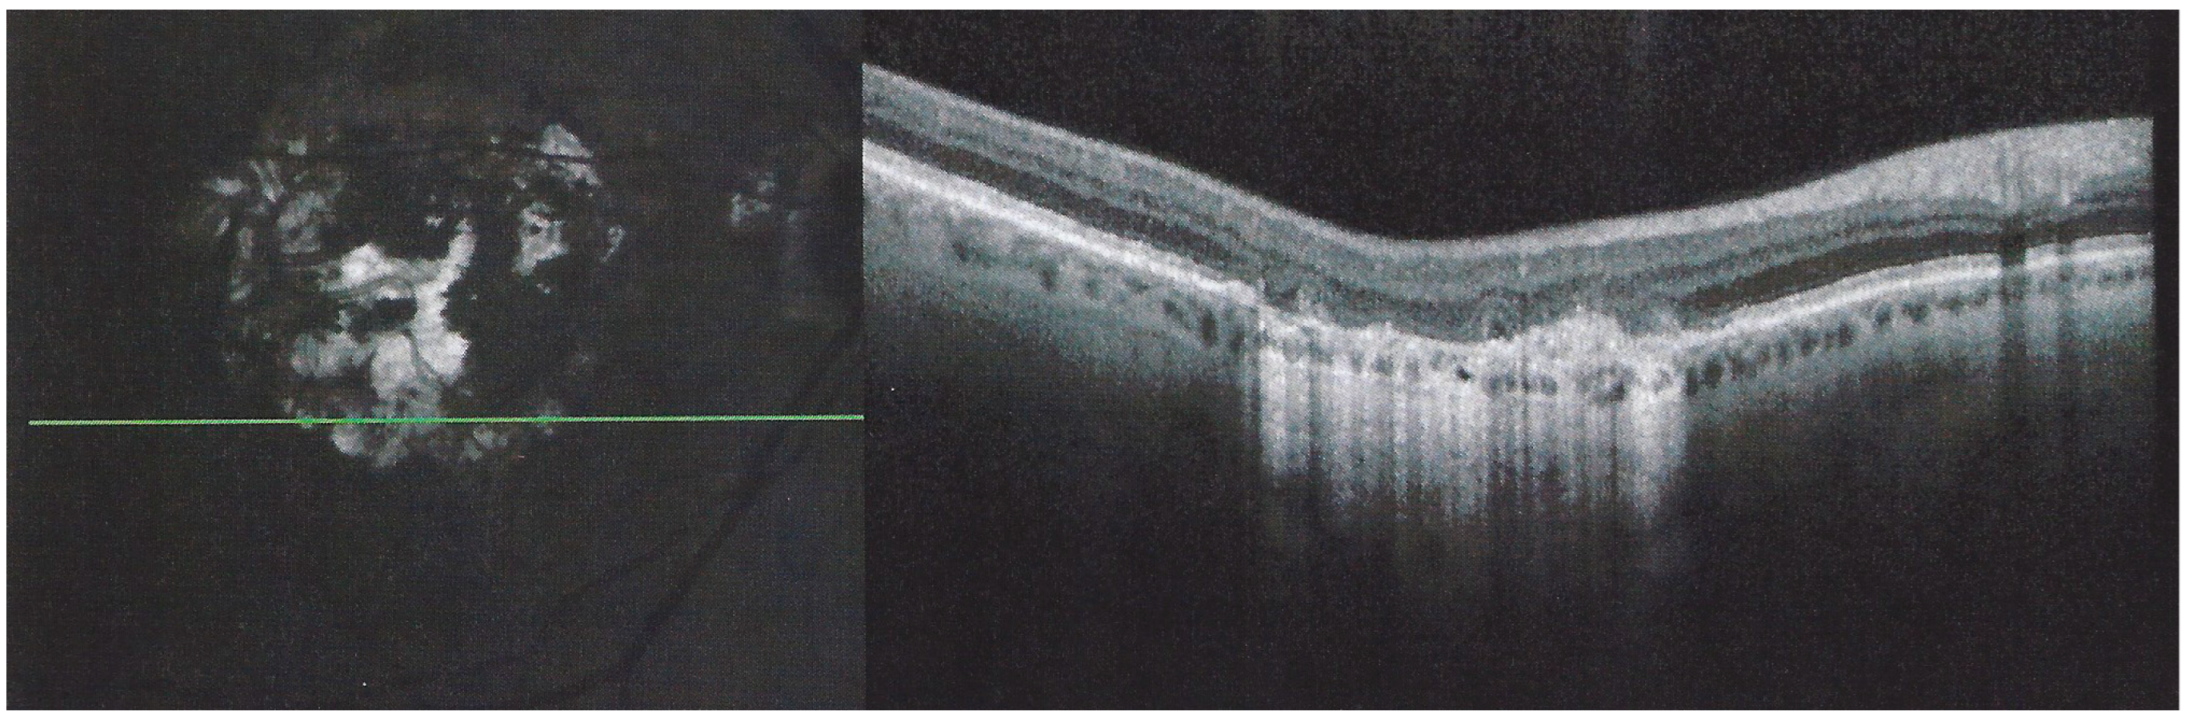

Figure 8. APMPPE/AMIC; SD-OCT in initial-acute phase OD (top) and OS (bottom) (same patient as Figure 5, Figure 6 and Figure 7a). In this initial phase, SD-OCT shows areas of hyperreflective changes visible in the outer plexiform layer and adjacent outer nuclear layer (arrows) but no loss of photoreceptor outer segments (see Figure 5).

The chorioretinal findings by spectral domain optical coherence tomography (SD-OCT) depend on the degree of involvement and the stage of the disease [5,7,25]. In early-acute disease ischaemia, induced by choriocapillaris non-perfusion, causes thickening of the outer retina including the IS/OS line and beyond (Figure 8). In later stages, SD-OCT can show either simple loss of photoreceptor outer segments, thickened RPE or atrophy with loss of RPE (Figure 9).

SD-OCT findings included thickened hyperreflective areas of the outer retina in the very early disease phase (10/35 eyes) (Figure 8 and Figure 11), photoreceptor outer segment loss and/or ellipsoid zone disruption-RPE alterations (22/35 eyes) (Figure 9), subretinal fluid (serous retinal detachment—SRD) (4/35 eyes), (Figure 14) and atrophy (3/35 eyes) in the late stage of the disease (Figure 15).